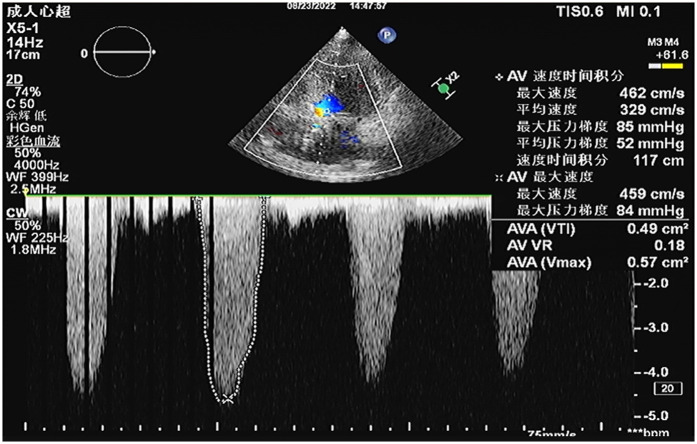

主动脉瓣狭窄(AS)经常与冠状动脉疾病(CAD)相关,特别是在治疗策略缺乏标准化临床指南的高危患者中。我们报告了一例严重AS和高危CAD患者,导致严重的心力衰竭,手术主动脉瓣置换术和冠状动脉搭桥术不适合,因为发病率和死亡率非常高。患者接受了体外膜氧合(ECMO)辅助经导管主动脉瓣置换术(TAVR)和经皮冠状动脉介入治疗(PCI)的一站式手术。术中患者先行预防性静脉-动脉ECMO置管,成功行右冠状动脉和左前降支PCI,然后行TAVR,无并发症。患者对手术的耐受性良好,血流动力学在整个过程中保持稳定。在一年的随访中,患者的心功能明显改善。本病例为治疗高危AS合并CAD提供了宝贵的经验,证明了该方法在临床实践中的可行性和有效性。

Aortic stenosis (AS) is frequently associated with coronary artery disease (CAD), particularly in high-risk patients for whom treatment strategies lack standardized clinical guidelines. We report a case of a patient with severe AS and high-risk CAD, leading to significant heart failure, for whom surgical aortic valve replacement and coronary artery bypass grafting were unsuitable because of very high risk of morbidity and mortality. The patient underwent a one-stop procedure combining extracorporeal membrane oxygenation (ECMO)-assisted transcatheter aortic valve replacement (TAVR) and percutaneous coronary intervention (PCI). During the procedure, the patient first received preventive veno-arterial ECMO placement, successfully underwent PCI on the right coronary artery and left anterior descending artery, and then TAVR was performed without complications. The patient tolerated the procedure well, with hemodynamics remaining stable throughout. At one-year follow-up, the patient's heart function was significantly improved. This case provides valuable experience in treating high-risk AS combined with CAD, demonstrating the feasibility and effectiveness of this approach in clinical practice.